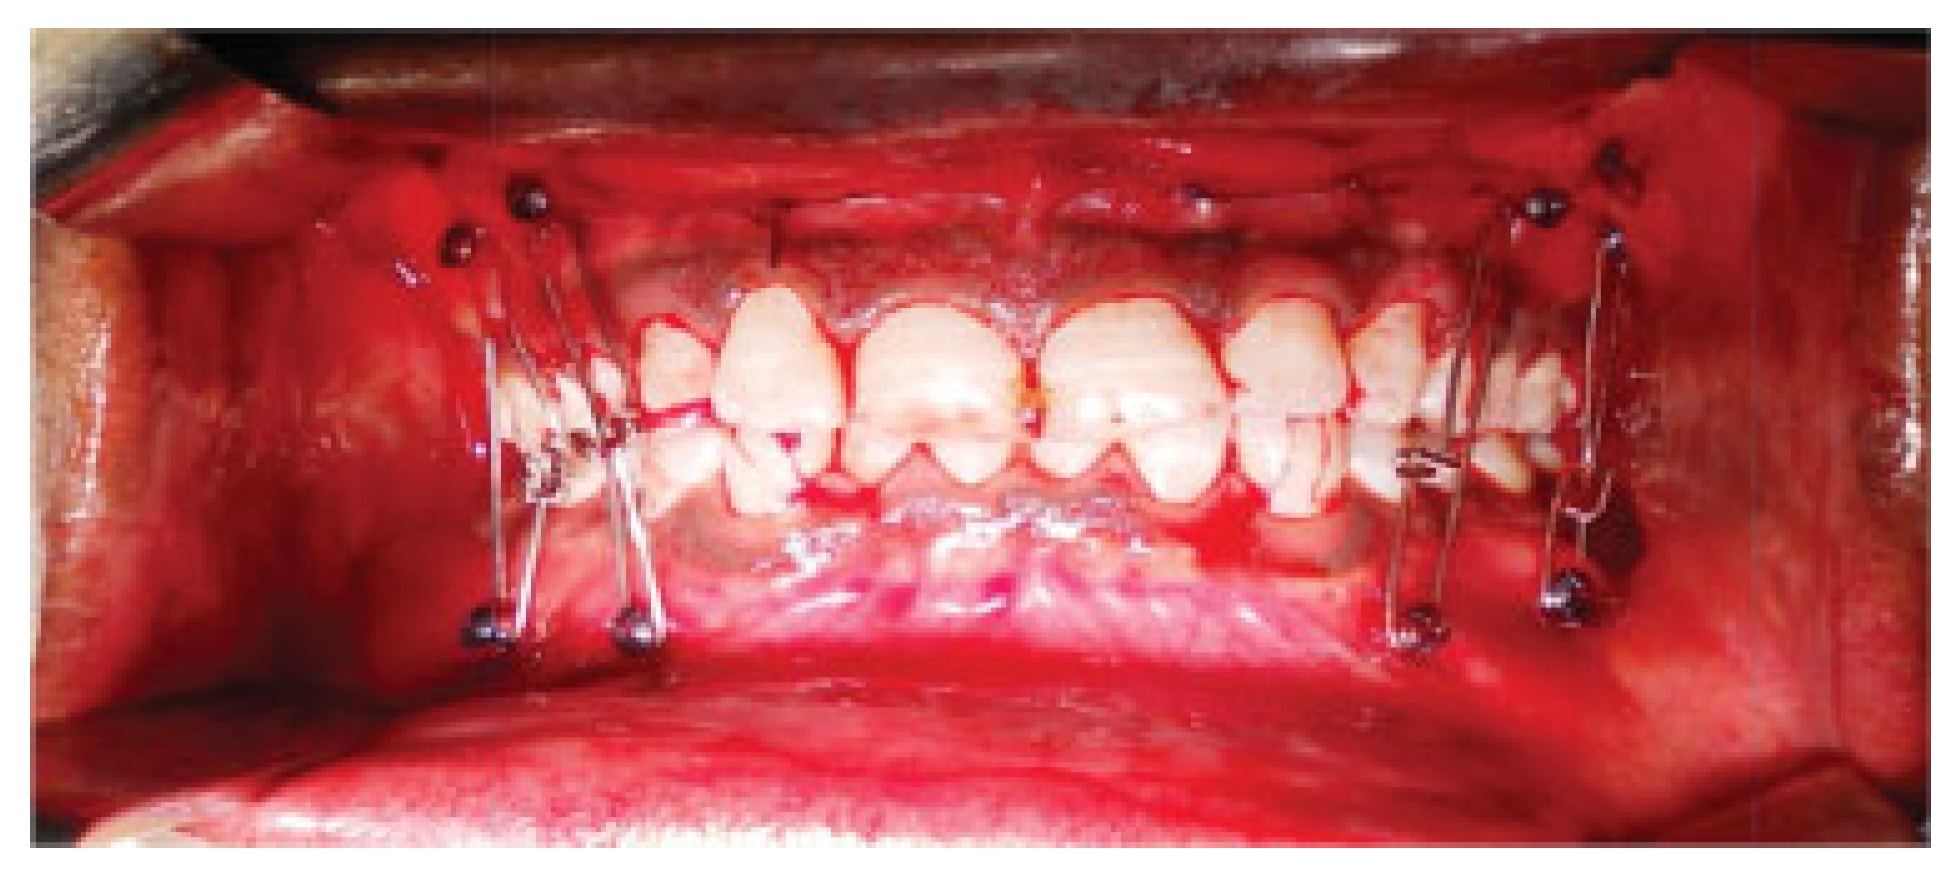

![]() |